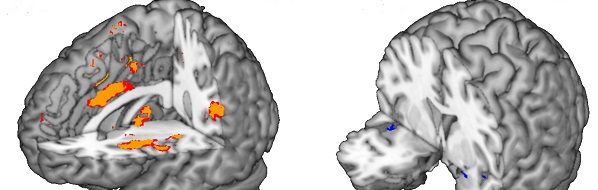

La méchanceté déclenche les mêmes réactions cérébrales que les mauvaises odeurs, L-FRII, 22.10.2020

La méchanceté déclenche les mêmes réactions cérébrales que les mauvaises odeurs, Yahoo Actualité, 22.10.2020

La méchanceté déclenche les mêmes réactions cérébrales que les mauvaises odeurs, Santé Magazine, 21.10.2020